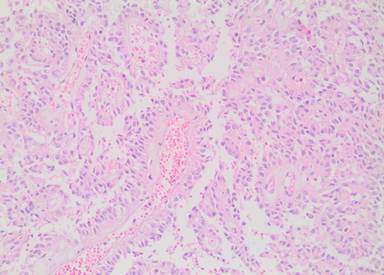

The pathological investigation showed a 13x12x11 cm pancreatic tumor, demarcated by a fibrous capsule and partial infiltration of fat tissue. Gross pathomorphology of the cut surface showed an inhomogeneous solid appearance with areas of bleeding and extensive calcifications. Microscopically, characteristic pseudopapillary formations were frequently observed (Figure 3). Pseudopapillae were formed when neoplastic cells drop away, leaving a variable number of cells surrounding delicate capillary-sized blood vessels. Immunohistochemistry was uniformly positive for vimentin (Figure 4) and CD 56 (Figure 5). Focal reactivity was detected for synaptophysin while negative reactions were found for chromogranin, neuron-specific enolase, CD10 and progesterone receptors. Proliferation index of Ki-67 was 1-2%. On the basis of these characteristic morphologic and immunohistochemical findings, the diagnosis of locally invasive solid pseudopapillary tumor of the pancreas was made. The pathologic investigation showed positive pancreatic resection margin for the tumor. For that reason re-resection of the pancreas was decided on a second look surgery. On April 2012 laparotomy was done and near total pancreatectomy was performed. The pathologic investigation for the second specimen showed negative pancreatic resection margin for tumor.

Figure 3. Microscopic findings of solid-pseudopapillary neoplasm on our biopsy specimen showing prominent pseudopapillary growth pattern (Hematoxylin and eosin, 20x high power field). |